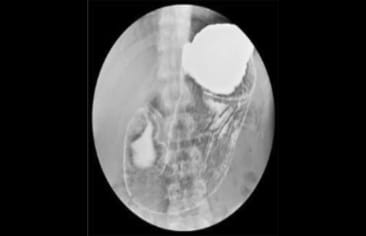

内視鏡検査とバリウム検査の比較

比べてみると内視鏡検査の方が画像が鮮明に見えることが分かります。

バリウム検査

日本消化器内視鏡学会ホームページより